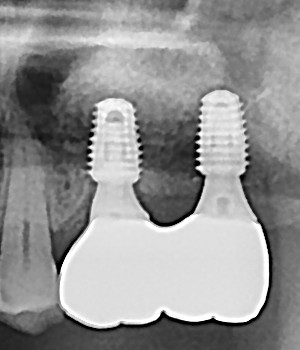

임플란트 뼈이식 + 임플란트